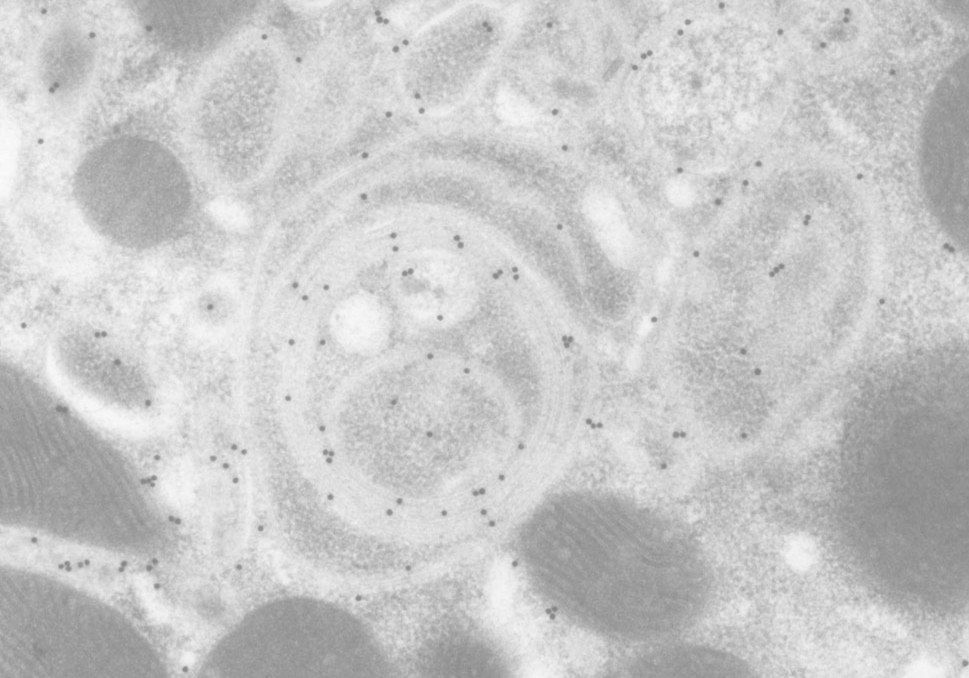

透射电子显微镜

TEM:Transmission Electron Microscopy

以最高水平的空间分辨率实现细胞内部的微观结构解析

Analysis of the fine structure of cells with high resolution